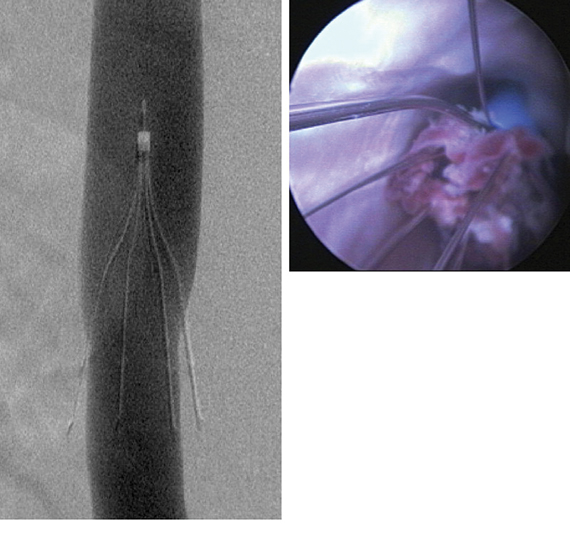

Ultrasound-facilitated endovascular thrombolysis 'a game changer' in acute pulmonary embolismApril 10, 2014StrokeDVT & Pulmonary Embolism